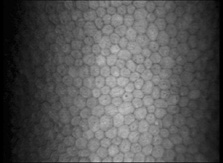

endothelium. Exp Eye Res 23:285, 1976 94. Amann J, Holley GP, Lee SB, et al: Increased endothelial cell density in the paracentral and peripheral regions

of the human cornea. Am J Ophthalmol 135:584, 2003 95. Bourne WM, Nelson LR, Hodge DO: Central corneal endothelial cell changes over a ten-year period. Invest Ophthalmol Vis Sci 38:779, 1997 96. Gallagher B: Primary cilia of the corneal endothelium. Am J Anat 159:475, 1980 97. Senoo T, Obara Y, Joyce N: EDTA. a promoter of proliferation in human corneal endothelium. Invest Ophthal Vis Sci 41:2930, 2000 98. Senoo T, Joyce NC: Cell cycle kinetics in corneal endothelium from old and young donors. Invest Ophthal Vis Sci 41:660, 2000 99. Joyce N: Proliferative capacity of the corneal endothelium. Prog Retin Eye Res 22:359, 2003 100. Sherrard ES, Ng YL: The other side of the corneal endothelium. Cornea 9:48, 1990 101. Rae JL, Watsky MA: Ionic channels in corneal endothelium. Am J Physiology 270:975, 1996 102. Rozsa AJ, Beuerman RW: Density and organization of free nerve endings in the corneal epithelium